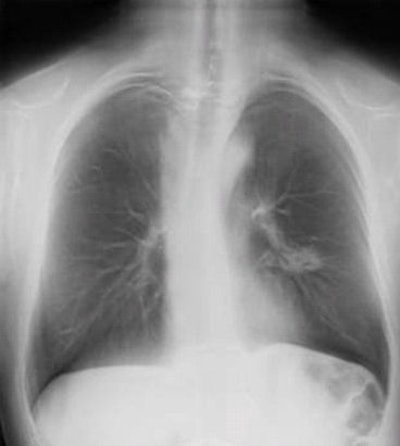

Digital chest tomosynthesis uses an upgraded DR system with a panning tube head. Image courtesy of Dr. Luca Bertolaccini.Results presented at both meetings have led the researchers to postulate that digital chest tomosynthesis could eventually be used as a sort of triage tool for chest screening of high-risk individuals, with suspicious or more complex cases referred for further examination with low-dose CT.